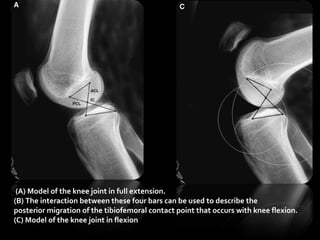

2) Four-bar kinematicchain Four-bar chain is rigid Zuppinger, Die active flexion, 1904 Four-bar chain is not rigid (PCL is lax in early flexion) Strasser, Lehrbuch der muskel, 1917 “Interactive knee”

• 71.

(A) Model ofthe knee joint in full extension. (B) The interaction between these four bars can be used to describe the posterior migration of the tibiofemoral contact point that occurs with knee flexion. (C) Model of the knee joint in flexion.

• 72.

Roll-back & Four-bar Axisof motion passes through the intersection of the bars